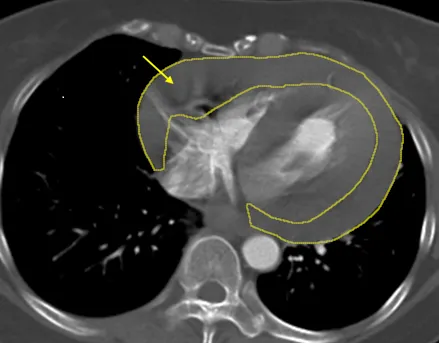

冠狀動脈鈣化

冠狀動脈氣球震波碎石術

心導管治療

血管鈣化治療

彰化秀傳紀念醫院

心臟支架